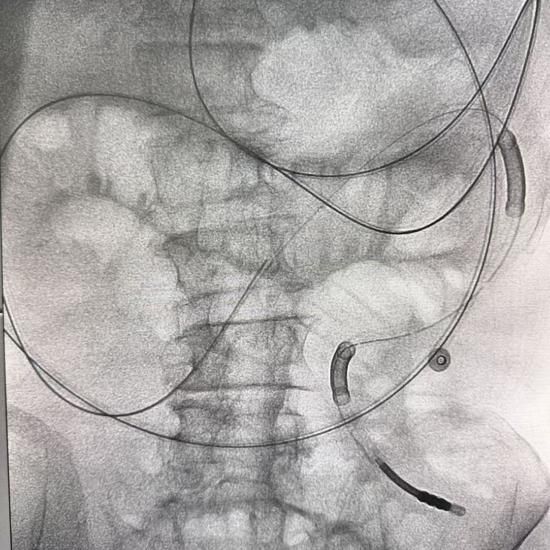

针对王大爷的复杂情况,贺伯伟主任多次组织科室讨论,全面评估老人的身体状况和病情严重程度及手术耐受度,最终决定采用一个突破性方案——DSA引导下肠梗阻导管置入术。这是一种微创介入技术,在数字减影血管造影的实时引导下,将一根细长的导管经鼻腔送入肠道,精准抵达梗阻部位上方,直接吸引积聚的肠内容物。既能快速减压,又避免了开刀手术的巨大创伤。

2月11日,手术顺利开展。贺伯伟主任与王志斌副主任医师凭借精湛技术,在DSA引导下精准操作,将导管稳稳置入预定位置。全程严谨把控每一个环节,确保导管位置准确无误。最终,手术顺利完成,老人的“关键通道”被重新打通。